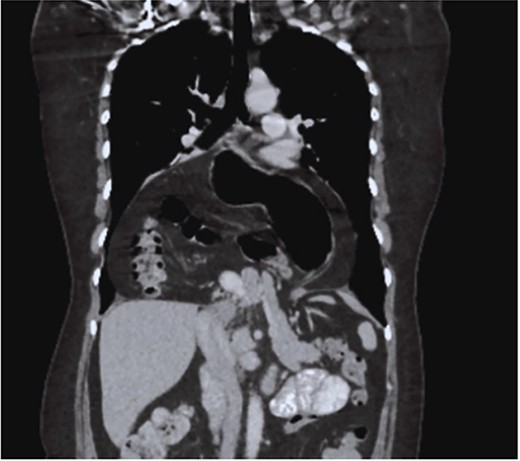

The case is reported of a 52-year-old woman, without significant illnesses, who presented with non-specific chest pain for 1 year, 6 months later with intermittent episodes of dyspnea with great and medium exertion, dysphagia, and heartburn. During the examination, hypoventilated lung fields at the bases, peristaltic sounds, and tympanism on percussion were heard. The thoracoabdominal tomography with contrast shows a diaphragmatic hernia containing the stomach, portions of the duodenum, pancreas, small intestine, and colon (Fig. 1), with a sac measuring up to 20 cm (Fig. 2).

CT in axial section, hernia sac measuring ~21 × 15 × 7 cm is observed.